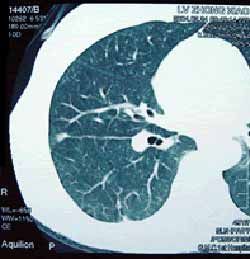

(一)中央型肺癌 發生在段支氣管以上至主支氣管的癌腫稱為中央型,約占3/4,以鱗狀上皮細胞癌和小細胞未分化癌較多見。

(二)周圍型肺癌 發生在段支氣管以下的腫瘤稱為周圍型,約占1/4,以腺癌較為多見。

(四)腺癌 女性多見,與吸菸關係不大,多生長在肺邊緣小支氣管的粘液腺,因此,在周圍型肺癌中以腺癌為最常見。腺癌約占原發性肺癌的25%。腺癌傾向於管外生長,但也可循肺泡壁蔓延,常在肺邊緣部形成直徑2-4cm的腫塊。腺癌富血管,故局部浸潤和血行轉移較鱗癌早。易轉移至肝、腦和骨,更易累及胸膜而引起胸腔積液。

細支氣管-肺泡癌(簡稱肺泡癌)是腺癌的一個亞型,發病年齡較輕,男女發病率近似,約占原發性肺癌的2%-5%,病因尚不明確。有人認為其發生與慢性炎症引起的瘢痕和肺間質纖維化有關,而與吸菸關係不大。其表現有結節型與瀰漫型之分。前者為肺內孤立圓形灶,後者為瀰漫性播散小結節灶或大片炎症樣浸潤,可能由於癌細胞循肺泡孔(Kohn孔)或經支氣管直接播散引起,亦有認為是多源性發生。它的組織起源多數認為來自支氣管末端的上皮細胞。電鏡檢查發現癌細胞漿內含有似Ⅱ型肺泡細胞內的板層包涵體。典型的本型癌細胞呈高柱狀,核大小均勻,無畸形,多位於細胞基底部。胞漿豐富,呈嗜酸染色,癌細胞沿支氣管和肺泡壁生長。肺泡結構保持完整,肺泡內常有粘液沉積。單發性結節型肺泡癌的病程較長,轉移慢,手術切除機會多,術後5年生存率較高。但細胞分化差者,其預後與一般腺癌無異。